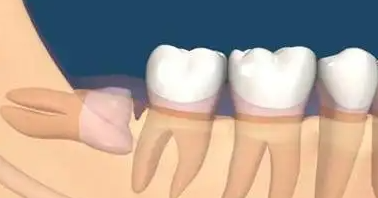

阻生牙,最常见于下颌第三磨牙,即智齿,是指由于邻牙、骨骼或软组织的阻碍,只能部分萌出或完全不能萌出,且本身位置或方向异常的牙齿。

水平阻生 :完全“躺平”,横着顶住前牙。

倾斜阻生 :呈一定角度,斜顶在前牙后背上。